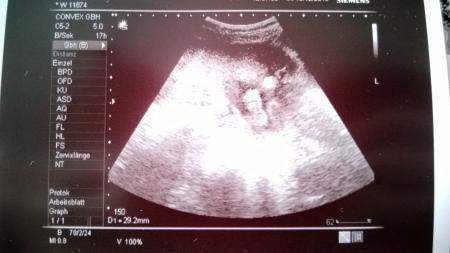

...... ein JUNGE ... Beweisbild hängt dran. Die Ärztin meinte falls es Abfällt sagt sie Bescheid. Nun gut dann wächst die Jungsrunde hier halt um noch ein Mitglied. Ich freu mich. Und der Papa der eigentlich gern ein Mädchen gehabt hätte freut sich auch über einen Jungen. Nun muss ich das nur noch meinem noch Jüngsten beibringen das es ein Brüderchen wird und kein Schwesterchen wie er sich gern gewünscht hätte. Leider kann ich euch nur sagen das er einen großen Fuß schon hat. 2,9 cm. Davon hab ich auch ein Bild. Er war sehr aktiv nachdem die Ärztin ihn etwas geärgert hat damit er mal die Beinchen öffnet. Das erfreulichste allerdings ist das der Cervix bei schönen 4,9 cm liegt. Daher ist momentan nichts von einer Insuffienz zusehen.

Die Bilder sind ja so klein. Ich lad sie nochmal einzeln hoch.